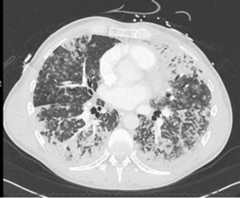

His vital signs on presentation were a temperature of 38°C, heart rate of 104 beats per min in sinus rhythm, and blood pressure of 147/88 mm Hg. His initial oxygen saturation (SpO2) was 90% on room air but he quickly progressed to needing a fraction of inspired oxygen of 80% via high flow nasal cannula to attain a SpO2 of 90–94%. A chest radiograph showed diffuse reticular nodular opacities throughout both lungs (Fig.1). His initial bloodwork showed signs of elevated inflammatory markers with mild leukocytosis at 11.1 × 109·L-1 (normal, 4.0–10.5 × 109·L-1) and C-reactive protein of 218.4 mg·L-1 (normal, 0.0–2.0 mg·L-1) but other results were noncontributory. His urine drug screen was positive for amphetamines, cocaine, fentanyl, and opioids. Due to progressive hypoxemic respiratory failure, he was intubated and admitted to the intensive care unit (ICU). Three nasopharyngeal swabs and a tracheal aspirate sample were all negative for SARS-CoV-2. He was treated with intravenous piperacillin-tazobactam, azithromycin, and vancomycin as well as methylprednisolone 40 mg twice daily. A computed tomography (CT) scan of the chest was performed on day 3 of illness and revealed extensive bilateral ground-glass and centrilobular nodular opacities without evidence of pulmonary embolism (Fig.2).

Fig. 2.

Axial slice of chest computed tomography showing extensive bilateral ground-glass and centrilobular nodular opacities on day 3 of illness

Bronchiolitis is often used to describe nonspecific inflammatory injury to primarily the small airways, often sparing a considerable portion of the interstitium.5 Although tissue biopsies were not taken for histopathology, there were bronchoscopic, clinical, radiographic, and microscopic features that supported the diagnosis of acute bronchiolitis. There is no direct laboratory test for inhalants available clinically, but our patient did admit to inhaling Freon a few days before his acute respiratory failure. Diffuse bronchial injury is supported by the bronchoscopic findings of copious bronchial secretions and later thick tracheobronchial casts. The obstruction of the airways from these secretions and casts led to increased airway resistance and worsening lung compliance shown by extremely low tidal volumes on pressure control ventilation, and near complete lung consolidation on chestx-ray. The casts examined under microscopy were mostly of inflammatory cells with no evidence of malignancy or infection. Moreover, the diffuse distribution of centrilobular nodules shown on CT further supported the nature of inhalational injury. His acute recovery and single system involvement make other inflammatory disorders much less likely.